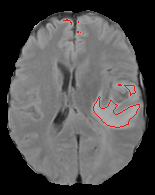

Fig. 2 presents the criteria used in the selection performance from a query image and an activation map from one learned filter. We compute the binarization of the activation map by using the Otsu threshold. Then, the performance is measured by the Dice score between the ground truth (GT) and the binary image.

Fig. 2 also presents examples of two activations (after the binarization), a ’bad’ and a ’good’ activation. Notice that the first one misses parts of the tumor, and then by selecting this image and learning filters from that, we get the second activation (good), capturing a more significant part of the tumor.